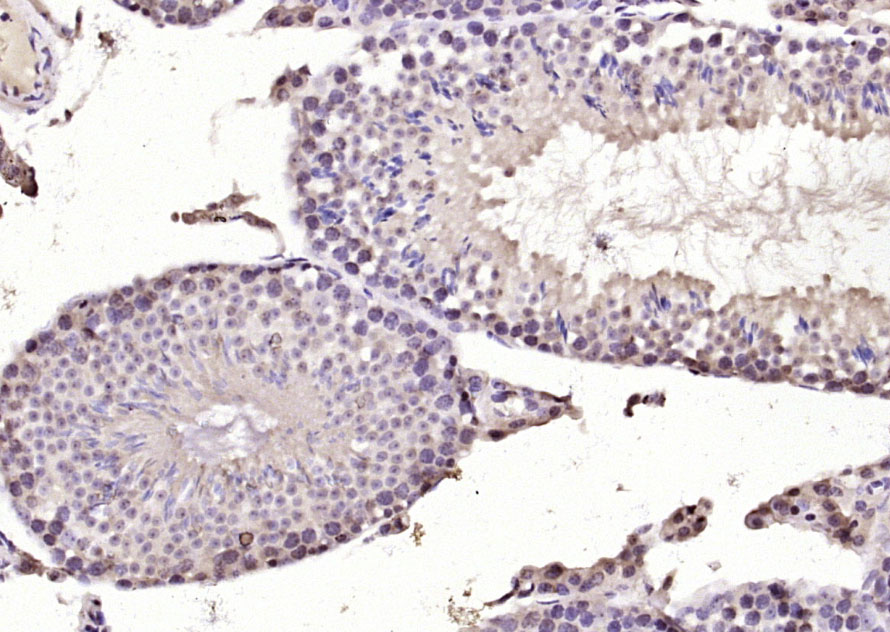

Paraformaldehyde-fixed, paraffin embedded (rat testis); Antigen retrieval by boiling in sodium citrate buffer (pH6.0) for 15min; Block endogenous peroxidase by 3% hydrogen peroxide for 20 minutes; Blocking buffer (normal goat serum) at 37°C for 30min; Antibody incubation with (DYRK2) Polyclonal Antibody, Unconjugated (bs-12332R) at 1:200 overnight at 4°C, followed by operating according to SP Kit(Rabbit) (sp-0023) instructionsand DAB staining.

Paraformaldehyde-fixed, paraffin embedded (mouse testis); Antigen retrieval by boiling in sodium citrate buffer (pH6.0) for 15min; Block endogenous peroxidase by 3% hydrogen peroxide for 20 minutes; Blocking buffer (normal goat serum) at 37°C for 30min; Antibody incubation with (DYRK2) Polyclonal Antibody, Unconjugated (bs-12332R) at 1:200 overnight at 4°C, followed by operating according to SP Kit(Rabbit) (sp-0023) instructionsand DAB staining.